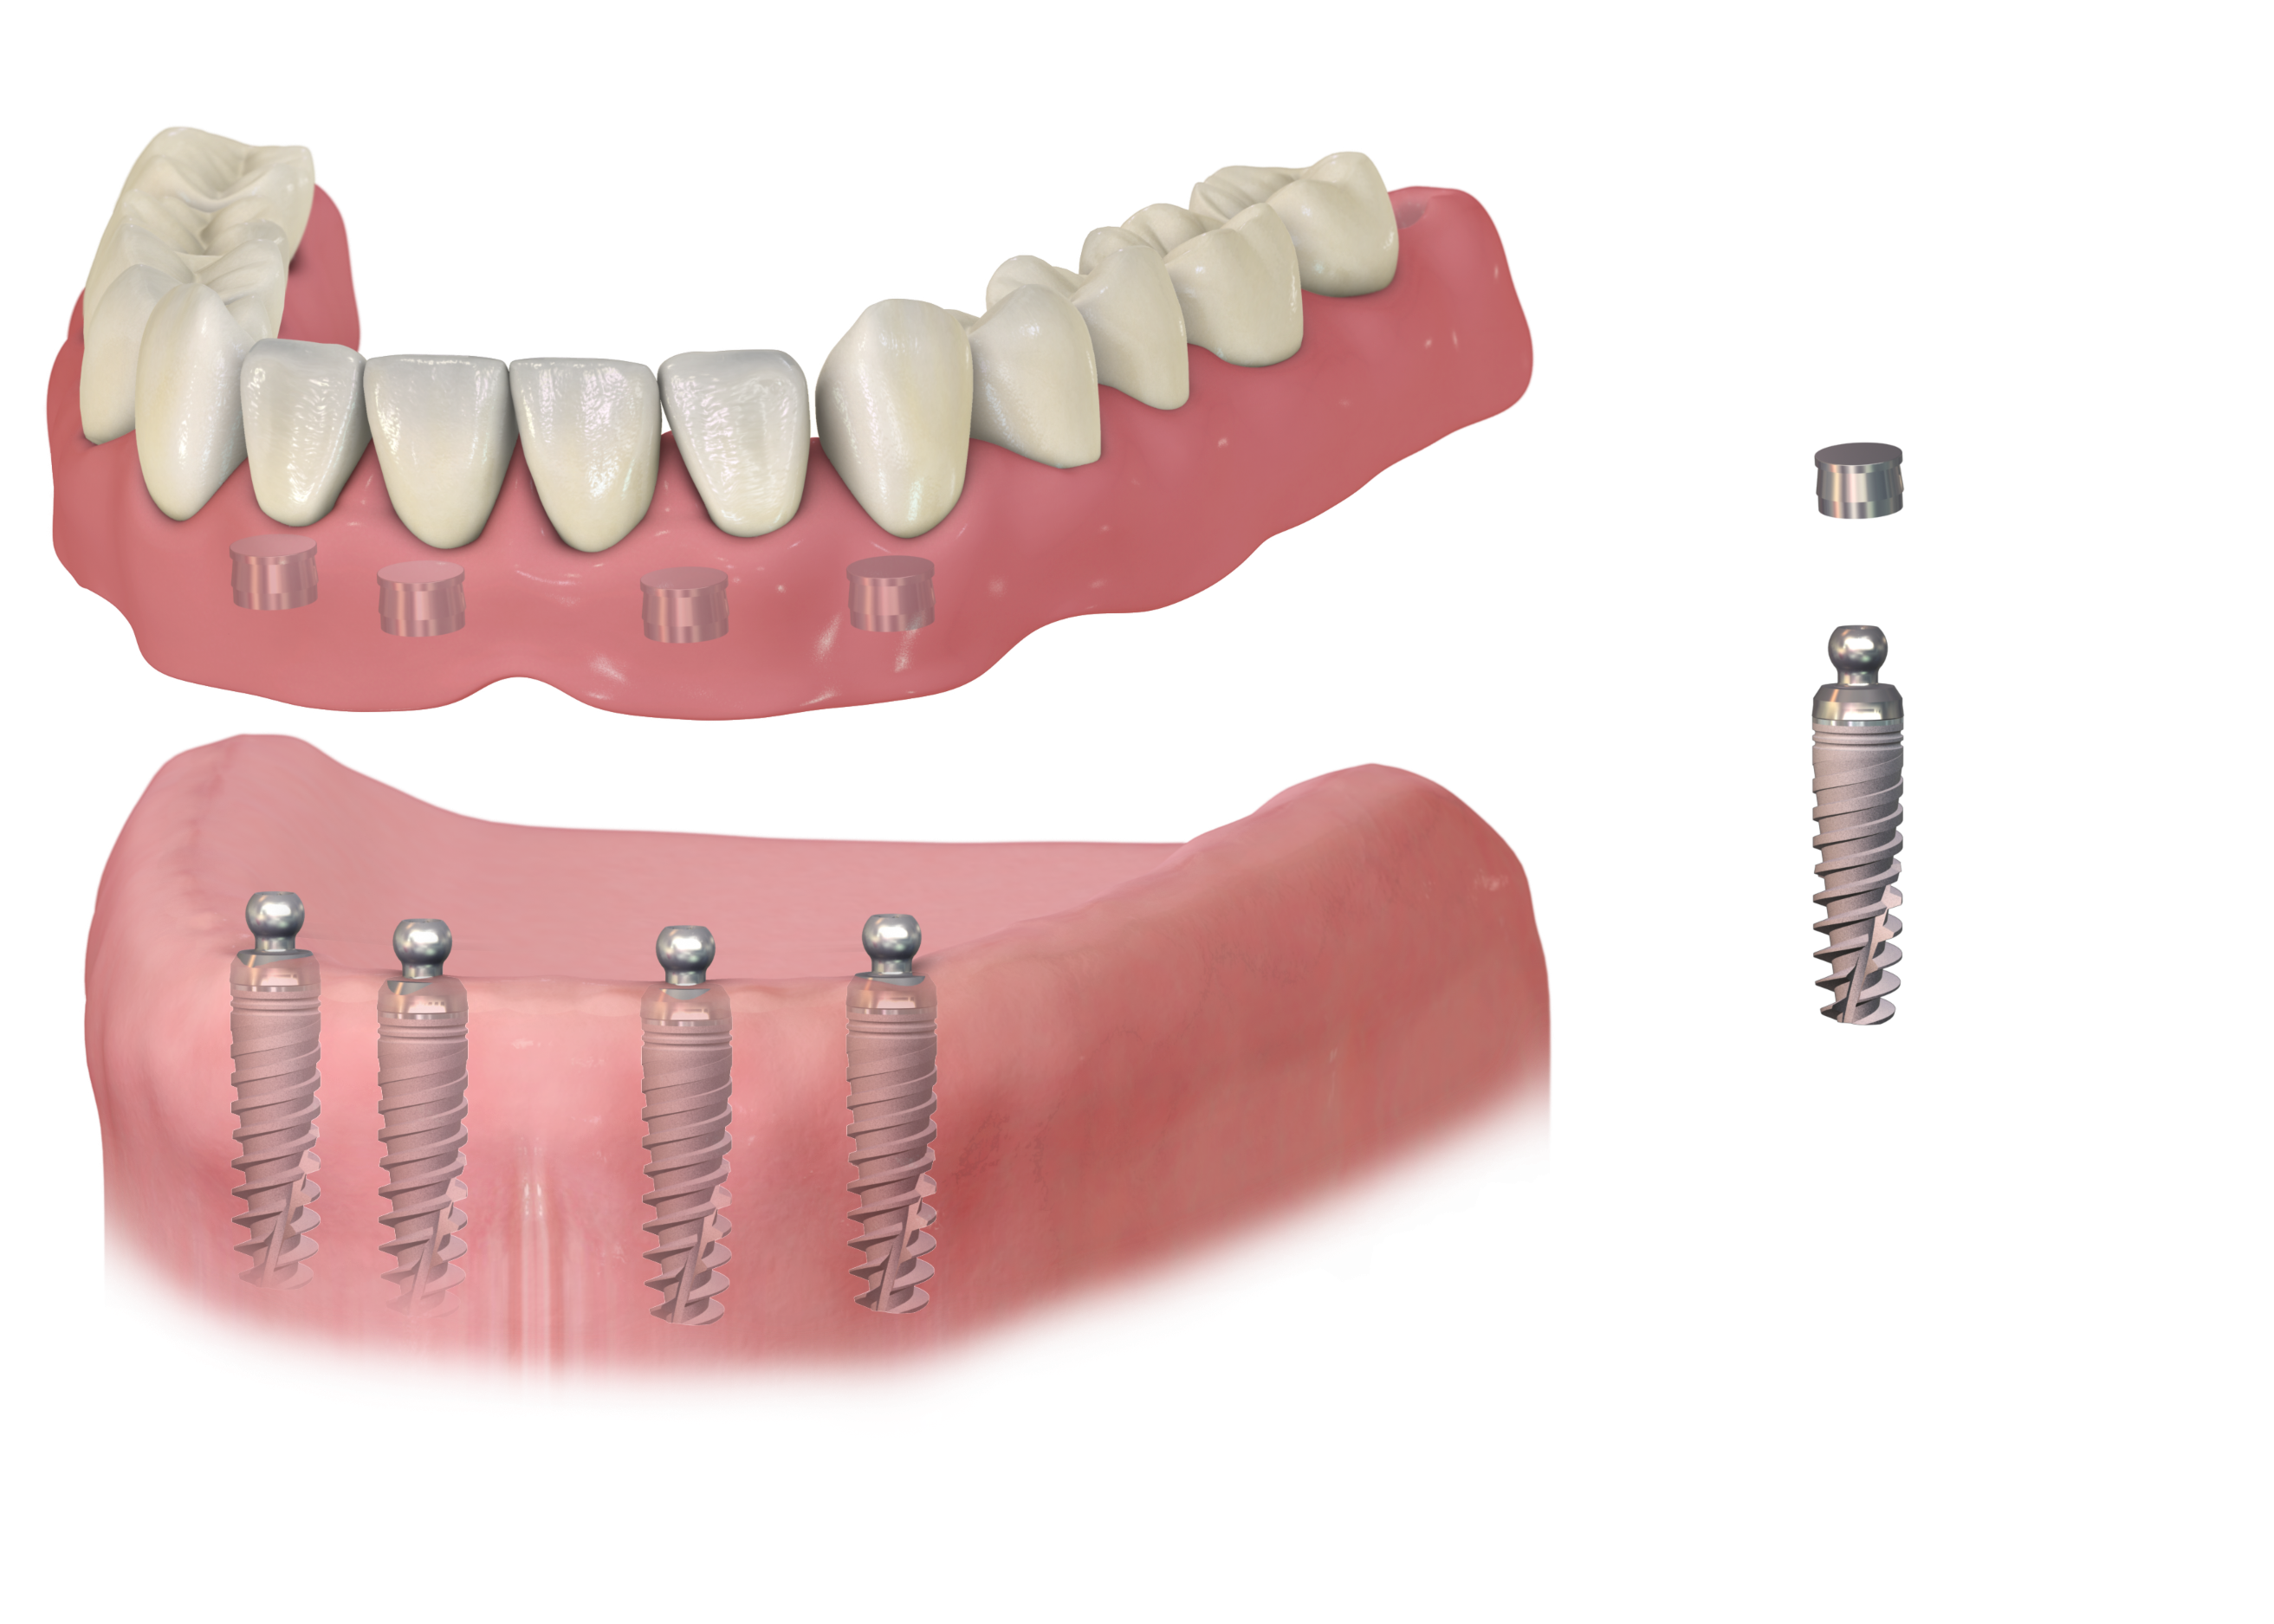

Современные съемные протезы на локаторах: Фото и примеры